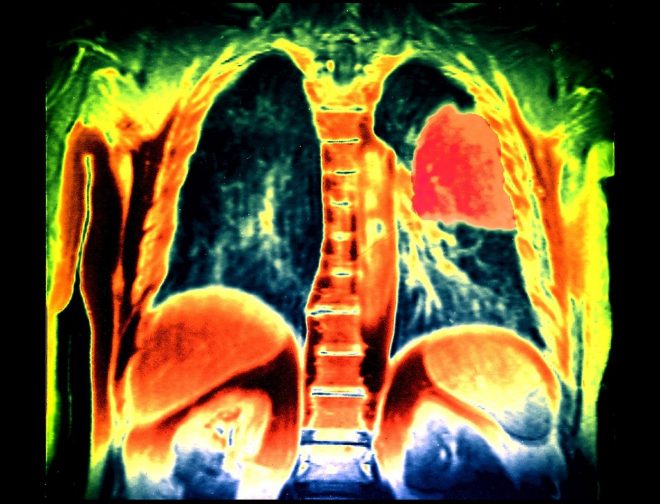

“Pljučni rak je še vedno ubijalec številka ena med raki. Na začetku bolezen nima specifičnih simptomov, zato je pomembno zgodnje odkrivanje in predvsem zdravljenje pljučnega raka,” je poudarila onkologinja Mirjana Rajer s Klinike Golnik. Kot je izpostavila, nikoli ni dovolj poudarjati, kako sta pljučni rak in kajenje povezana. V bistvu današnje število bolnikov s pljučnim rakom po njenih navedbah odraža kadilske navade 20 ali 30 let nazaj. Če bomo zmanjševali kajenje, bo čez 20, 30 let tudi manj bolnikov s pljučnim rakom, je ocenila.